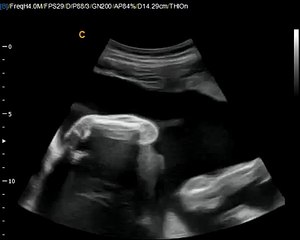

12 Weeks Pregnant Gender Determination Ultrasound

85 chance its a girl - determined at the end where the cursor is pointing\rbr\rbr*confirmed 100 at 20-week ultrasound